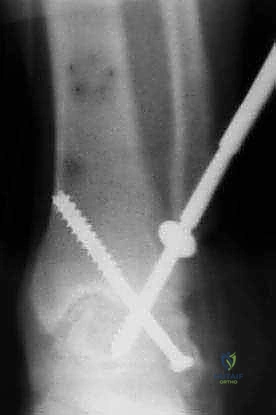

- التثبيت الصلب (Rigid Fixation): يتم تثبيت العظام في وضعيتها الجديدة باستخدام مسامير طبية كبيرة مجوفة (Cannulated Screws) مصنوعة من التيتانيوم. يتم إدخال هذه المسامير عبر العظام بتقنية متقاطعة لضمان أقصى درجات الثبات والضغط بين السطحين العظميين.

- الترقيع العظمي (Bone Grafting): لتعزيز الالتئام، يتم استخدام الجزء الذي تم قطعه من عظم الشظية وتثبيته كجسر داعم عبر المفصل المدمج، أو يتم طحن أجزاء من العظام الزائدة واستخدامها كطعم عظمي ذاتي لملء أي فراغات.